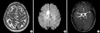

Diffusion- and T2-weighted MRI revealed a hyperintense lesion in the callosomarginal territory of the right anterior cerebral artery, and MR angiography did not show significant stenosis on the intra- and extracranial artery (Fig. 1).